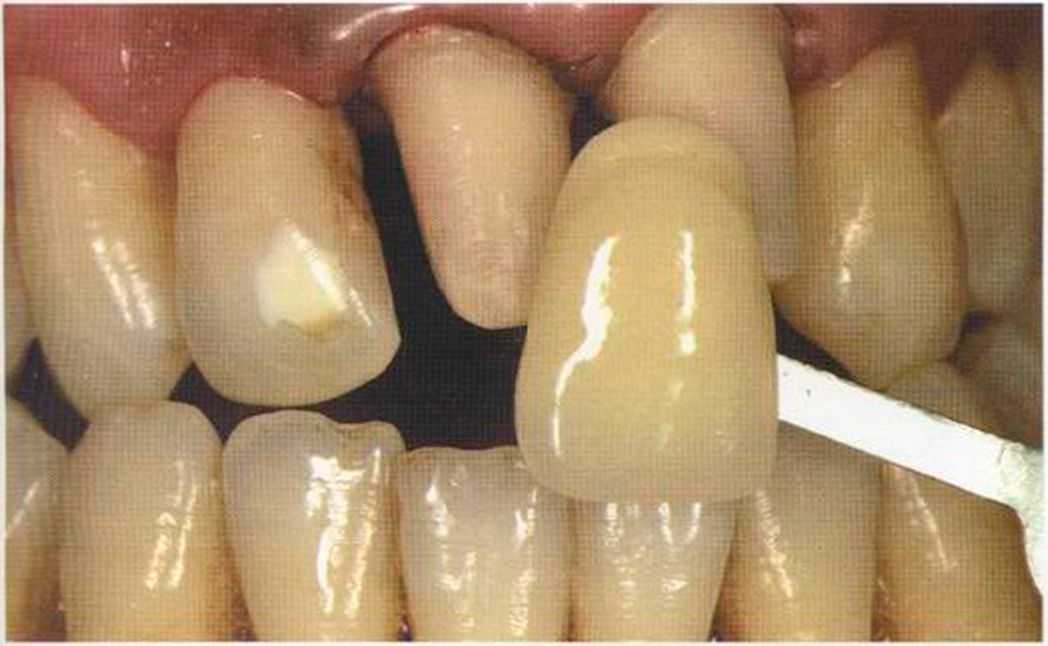

После того как мы определит цвет зуба, решено быо сначсьа изготовить одну коронку.

Результат с использованием In-Ceram развеял все сомнения, и решение об изготовлении коронки на другой боковой резец не заставило себя долго ждать.

Первое лечение проходию много лет назад у другого доктора. Со временем ос те пи / ка уху дин ьась, особенно в пришеечной области. Этот пациент хотел новые коронки в области 12 и 22, по сомневсься, нас кол ько хорошо они будут выглядеть.